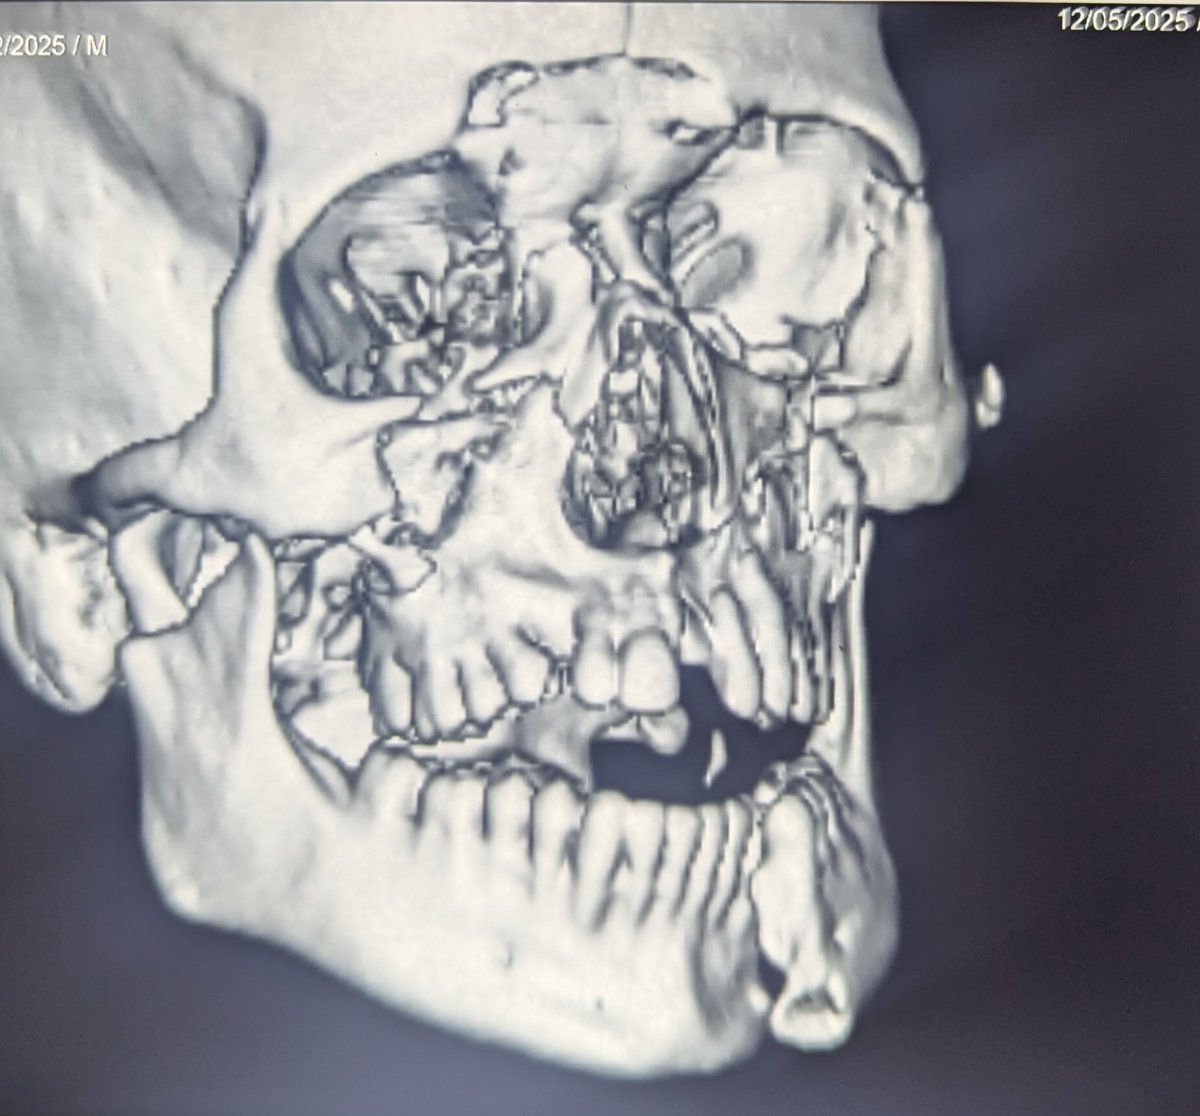

28 Male Head-on collision of two wheeler with lorry. No helmet. CT: Pneumocephalus Intraventricular hemorrhage Fracture of almost every facial bone Fracture ribs. No hemo, pneumothorax Liver lacerations. AAST 4. On receiving in the ICU, E4M6 Vitals stable Mouth opening